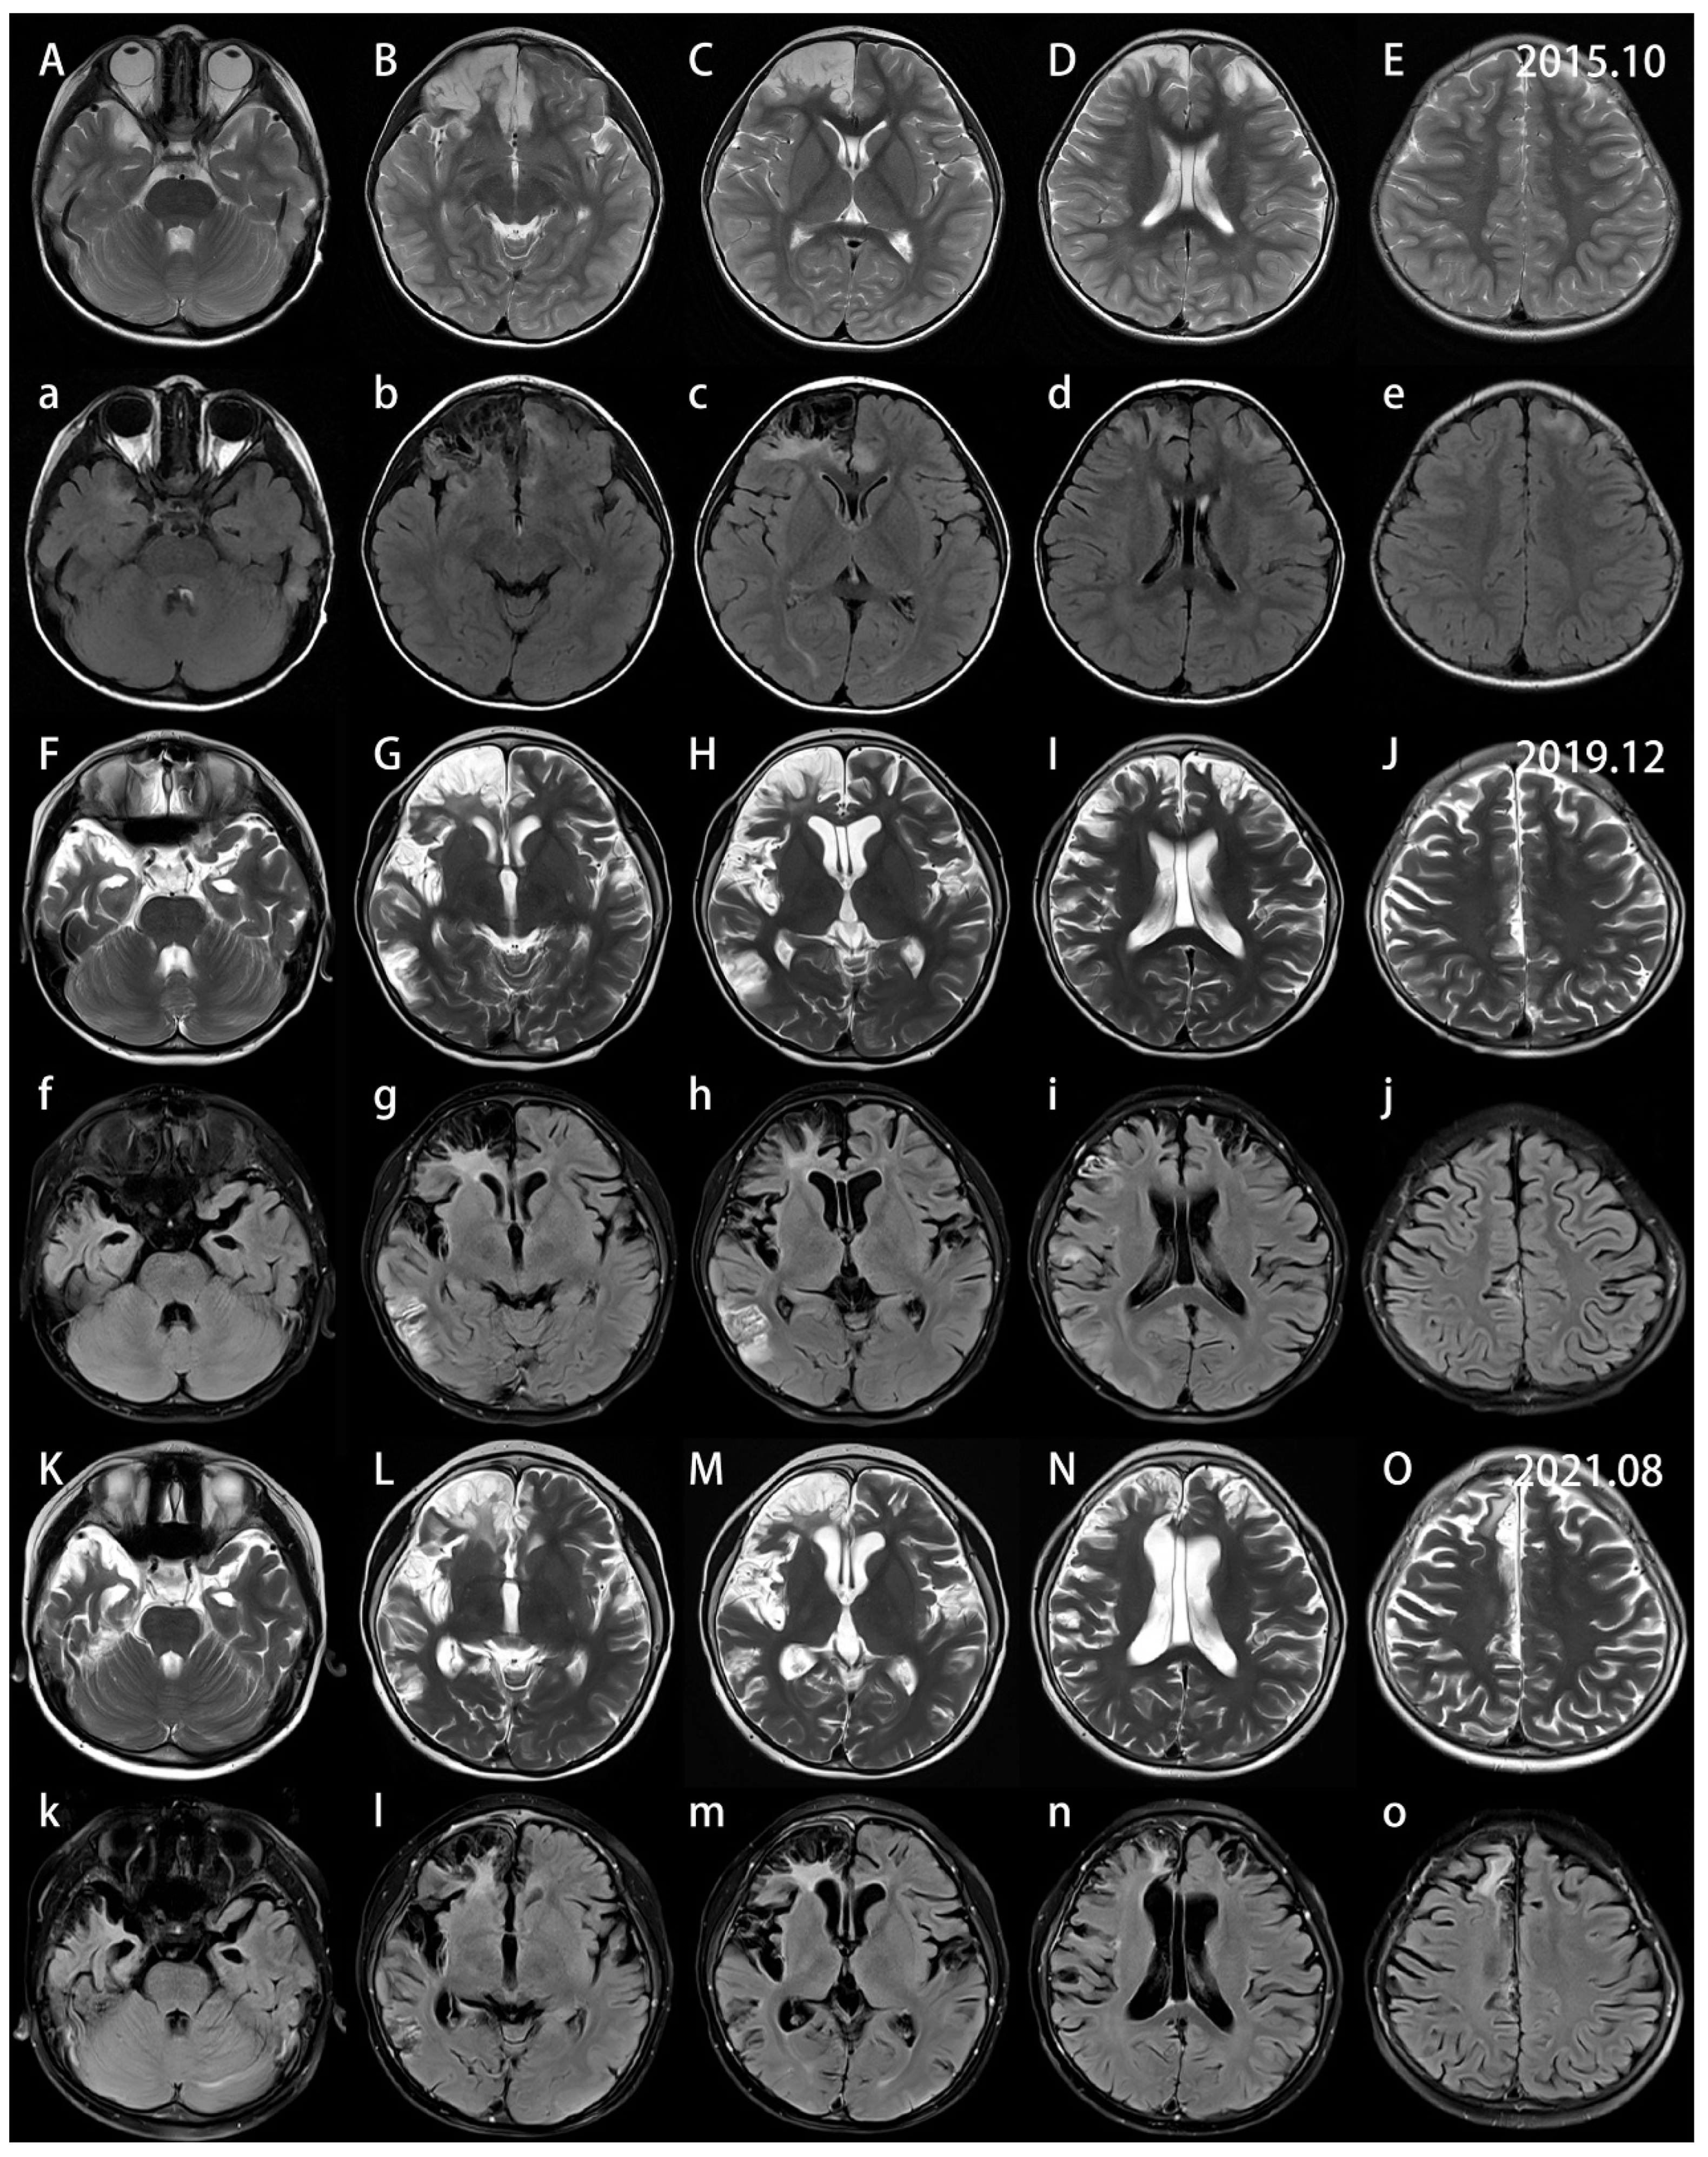

2. Case Report